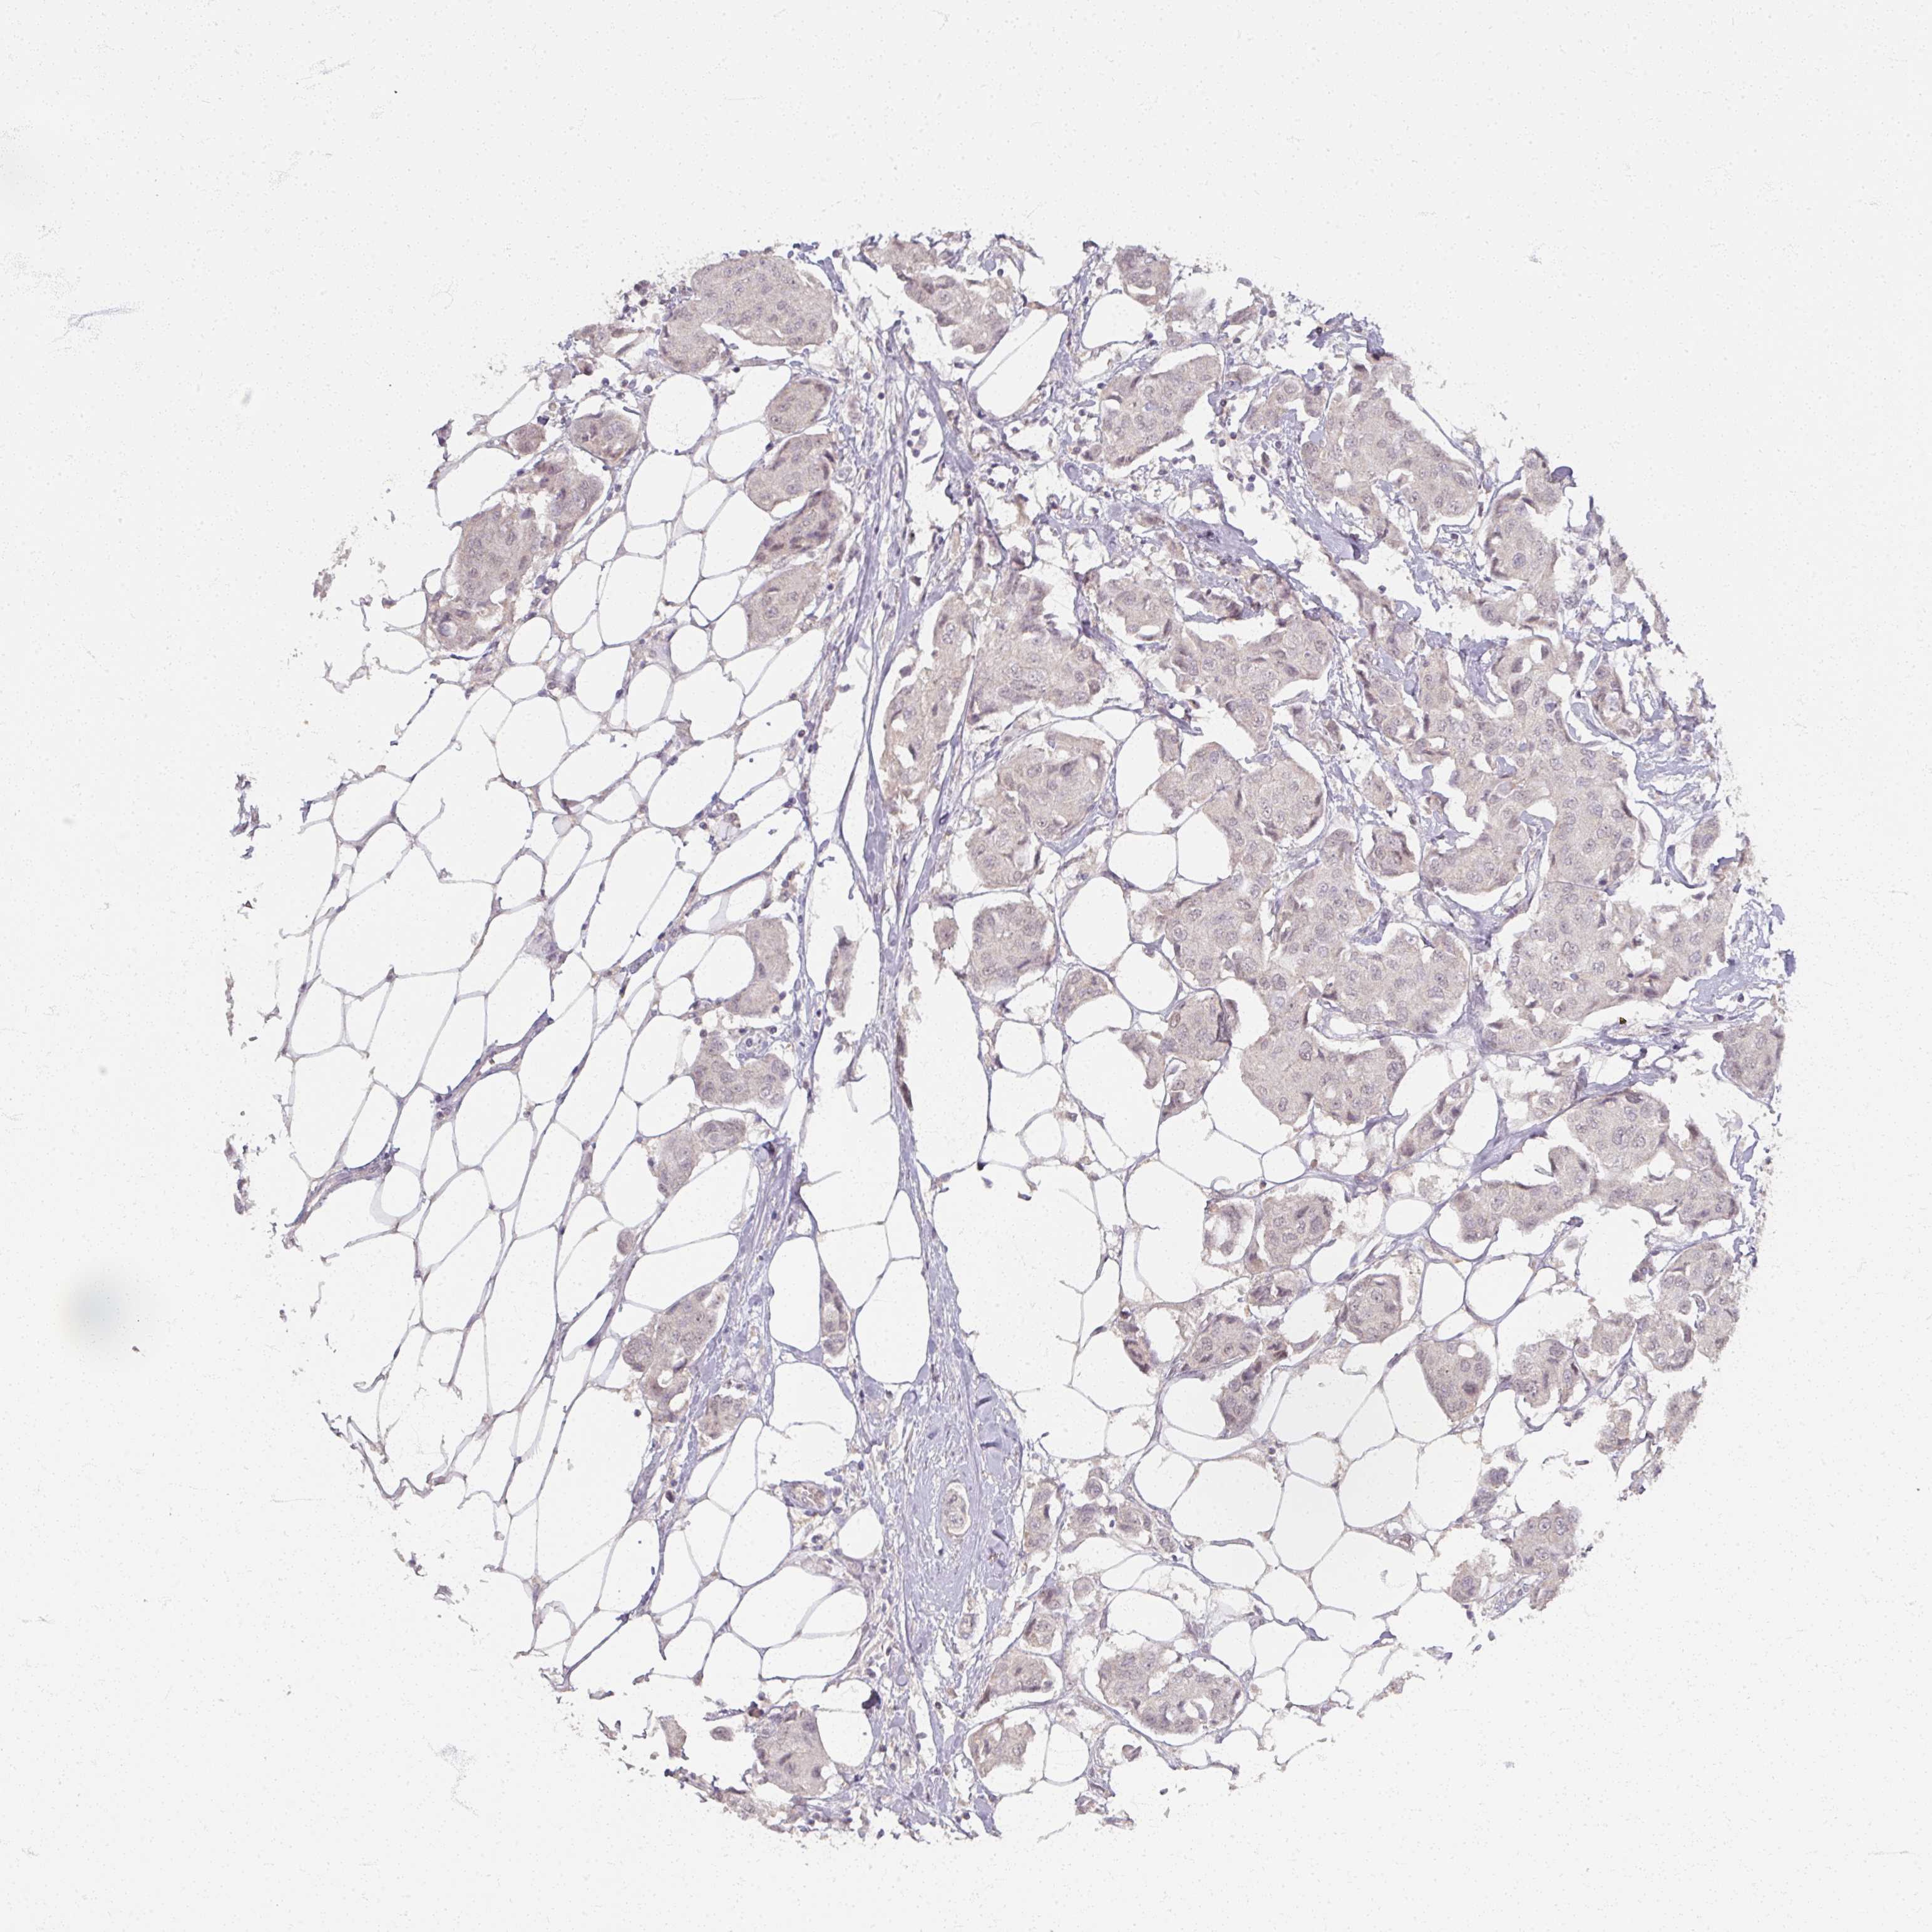

CANCER BREAST CANCER Show tissue menu

BRCA TCGA BRCA VALIDATION PROTEIN EXPRESSION

Breast cancer

Human cancer

Breast invasive carcinoma